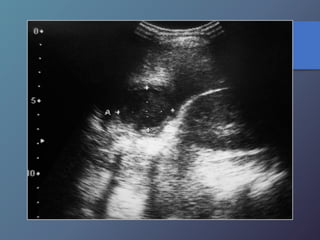

Traumatismo Hepático

• La lesión hepática es a predominio del lóbulo derecho.

• Mayor particularidad en segmento posterior.

• Mayor frecuencia por laceración peri vascular.

• Se producen hematomas subcapsulares,

pericapsulares o aislados.

• La hemorragia en las primeras 24 horas es ecogénica y

posteriormente se hace mas hipoecogénica.

• Entre las dos o tres semanas se puede observar gran

cantidad tejido de granulación.